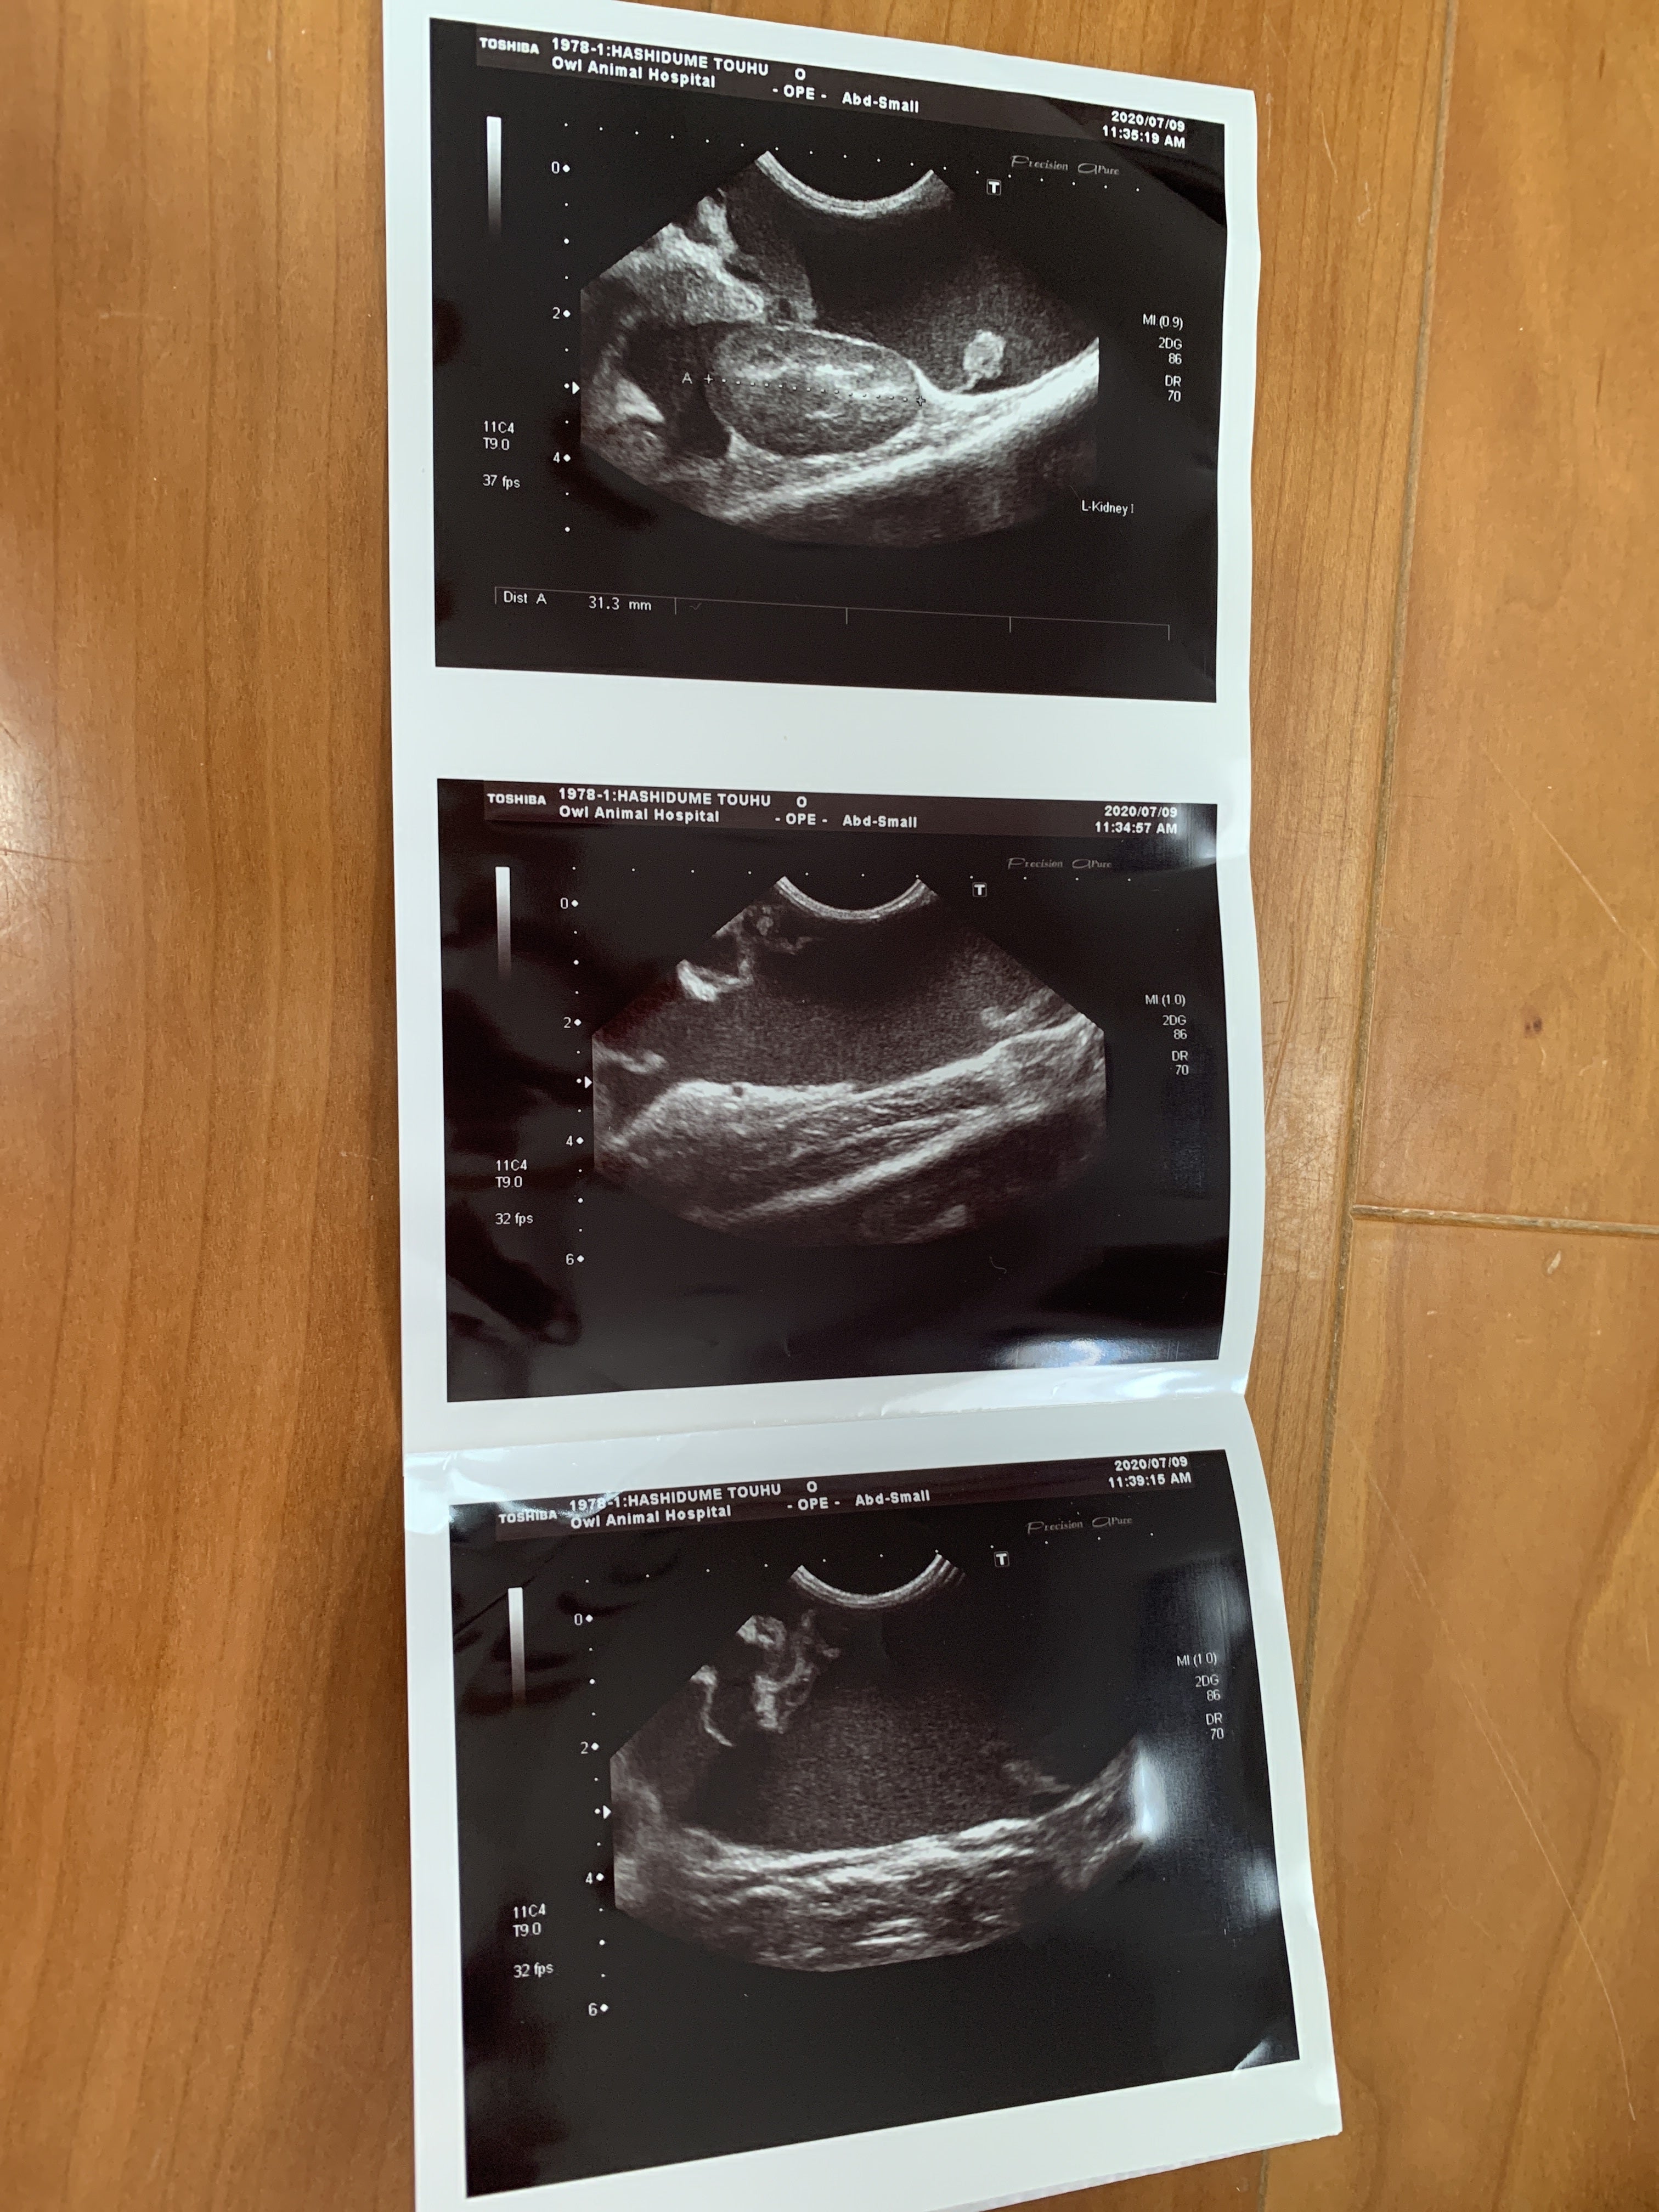

7月9日 朝から病院に連れて行きました。血液検査とエコーの結果

ここで初めて猫伝染性腹膜炎かも知れないと言われました。少しお腹が膨らんでいるのは便秘ではなく腹水でした。私は初めてその病名を聞きました。先生が言うには、このFIP と言う病気は進行が早く数日〜2か月で亡くなる怖い怖い病気ですとの事でした。その後の先生の話を涙が流れるのを必死にこらえて聞いていました。

ウェットタイプは腹水が溜まっていくので、見た目も分かるし、腹水を使った検査でFIP と分かるので診断が早い。